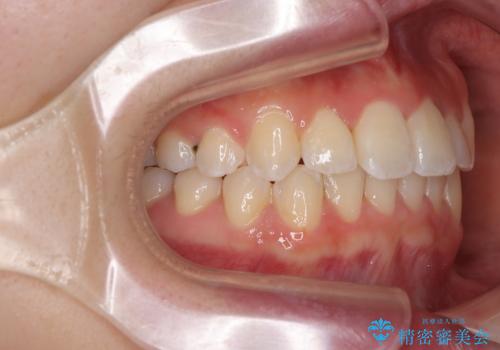

前歯のクロスバイト 裏側に隠れた歯をワイヤー装置で短期間治療

- 上顎前歯のクロスバイトを気にして来院された患者様です。

ワイヤー矯正でもマウスピース矯正でも対応可能でしたが、マウスピースによる自己管理に一切の自信がないとのことで、ワイヤー装置にて矯正治療を行うこととしました。

装置の外見を気にしていましたが、短期間で治療を終えることができるだろうと伝えると、安価であるメタルブラケットを選択されました。

想定通り、1年強で綺麗に仕上げることができました。